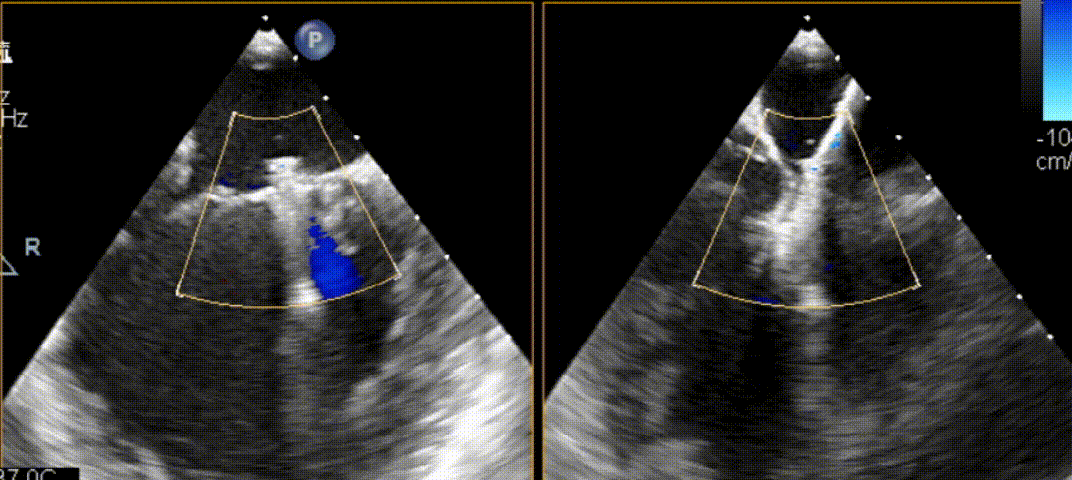

邓捷教授在食道超声的引导下将可操控导引导管(SGC)和二尖瓣夹输送系统(CDS-XTR)送入左心房,并成功将XTR推送至左心室瓣叶下方,并捕获夹合后成功释放。术后彩色多普勒显示2/1区术前的大量反流几乎消失,平均跨瓣压差为1mmHg,且患者的肺静脉逆流即刻得到改善。

XTR闭合后,彩色多普勒下反流几乎消失